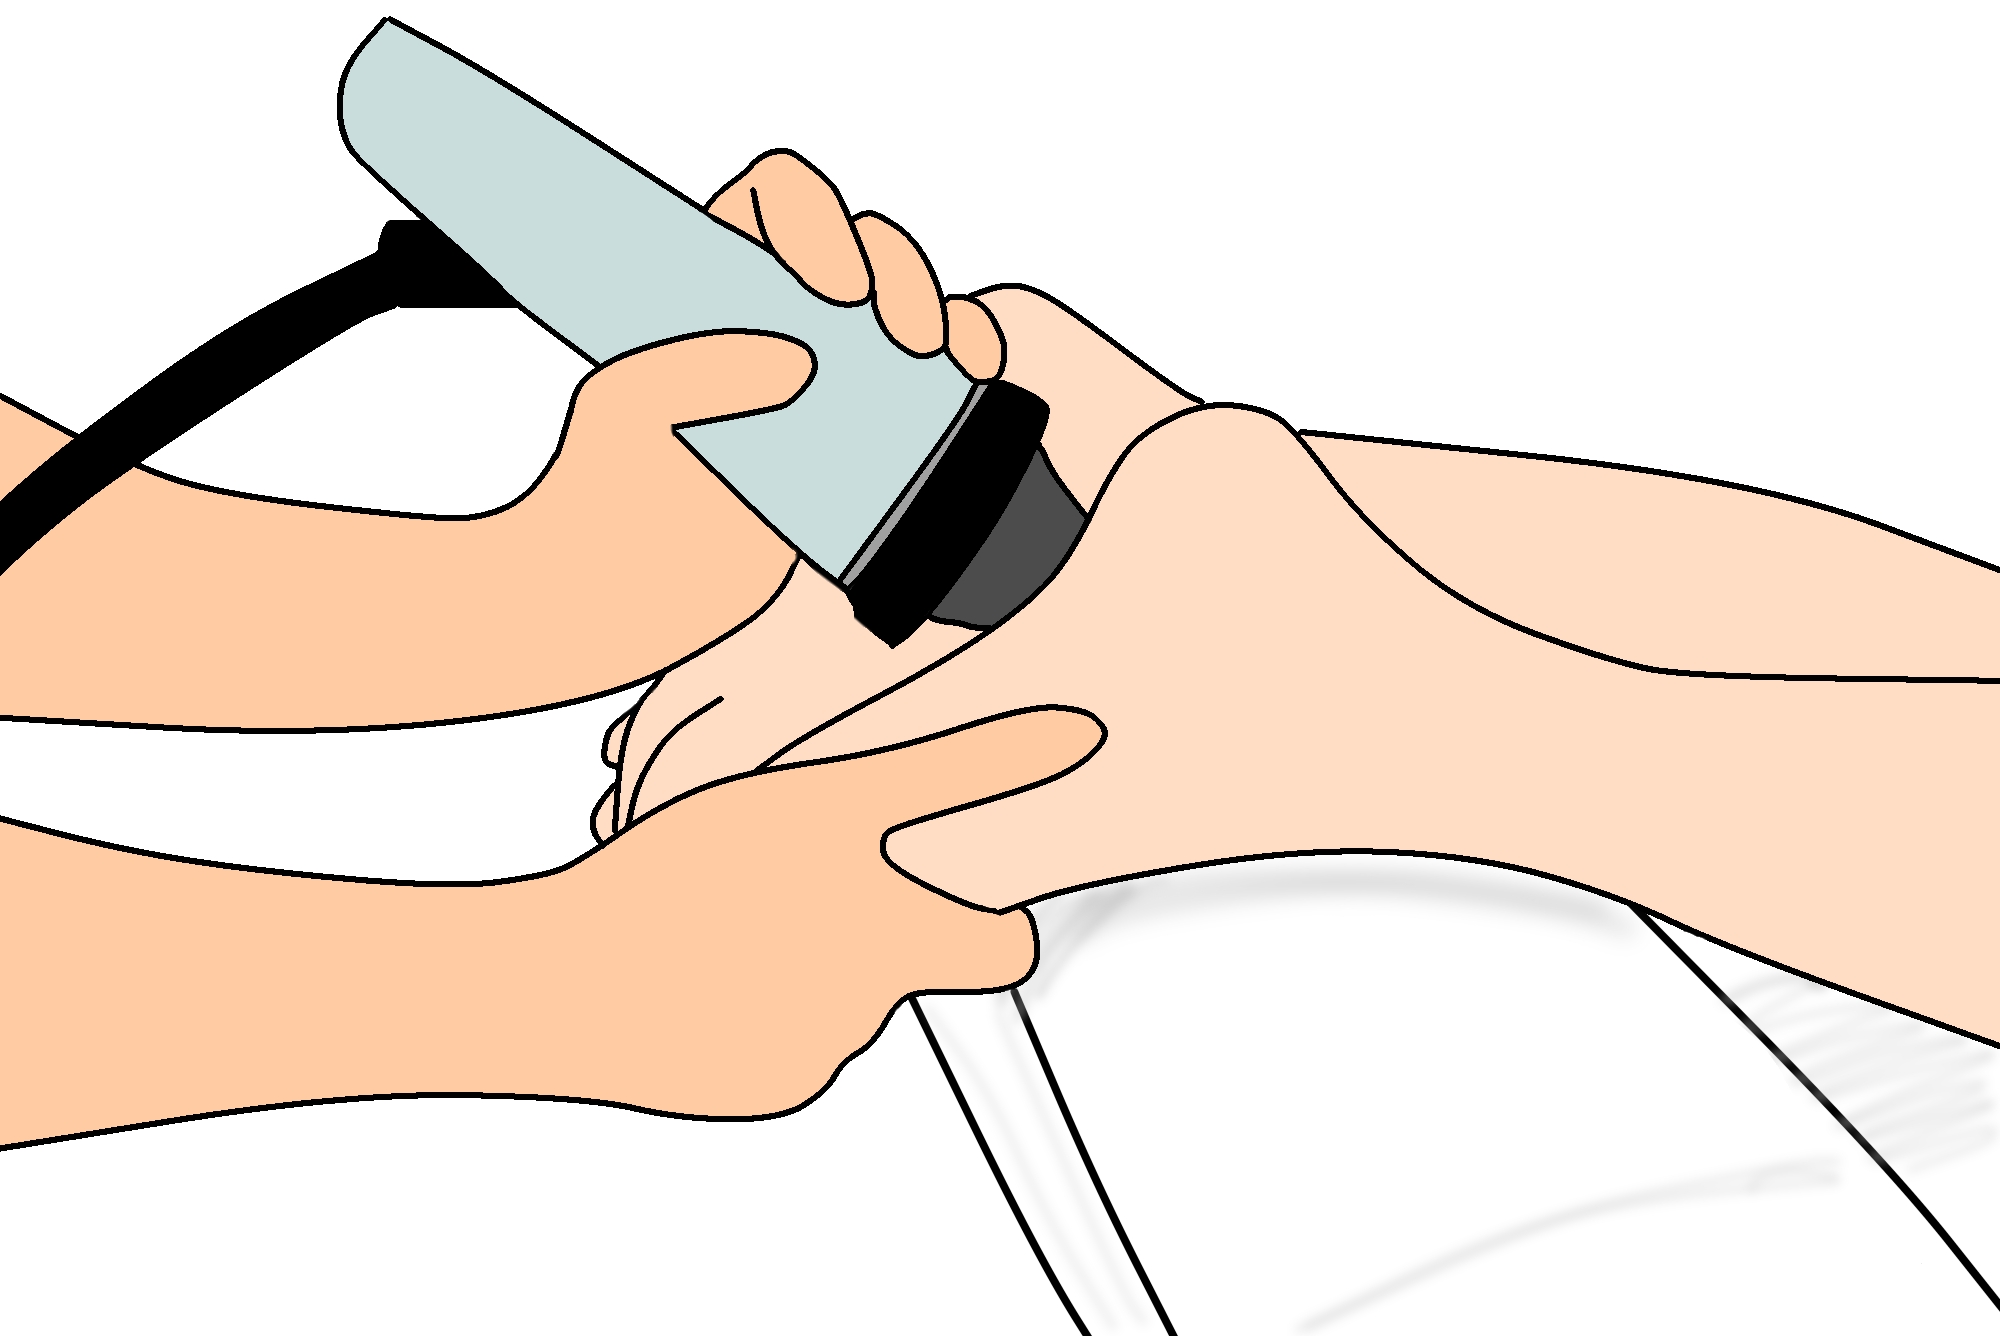

衝撃波療法では、医療専門家が体の炎症を起こした領域に超音波エネルギーの浸透波を当て、その領域に微小外傷を引き起こします。この微小外傷は体の治癒反応を促します。

衝撃波療法は非侵襲的であり、体の外側で行われます。外来での施術となりますので、施術終了後はそのままご帰宅いただけます。

施術時間は片足あたり10分~20分程度です。

衝撃波がかかとに浸透すると、軽い不快感を感じる場合があります。足底筋膜炎の痛みの重症度に応じて、さらに 2 ~ 4 回の衝撃波セッションを受ける必要がある場合があります。